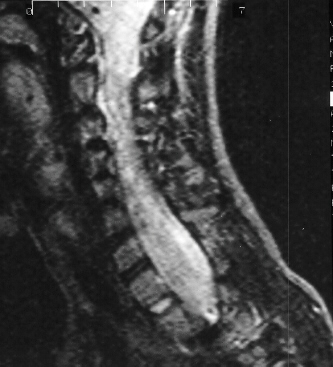

In preparation for spinal fusion for stabilization of this kyphoscoliosis he underwent a MRI of the brain cervical and thoracic spine and CT of the thorax. The brain and cervical spine showed no evidence of tumor. The lower cervical and upper thoracic canal was enlarged without evidence of cord compression, a finding consistent with dural ectasia . There is soft tissue protrusion into the thoracic canal that may resemble a dumbbell lesion.